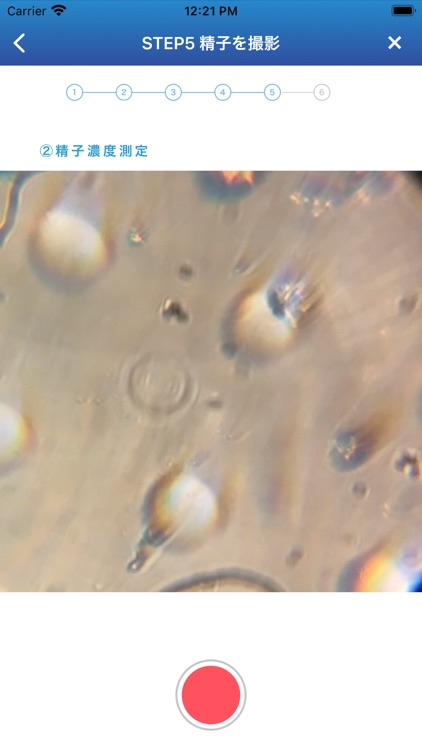

dotest! (ドゥーテスト)は、スマホを使って、ご自宅で簡単に高精度に運動精子濃度をチェックできるアプリです。

dotest! (ドゥーテスト)は、スマホを使って、ご自宅で簡単に高精度に運動精子濃度をチェックできるアプリです。

本製品では、検体中に元気な精子=運動能力のある精子がどのくらいいるのかを算出できます。